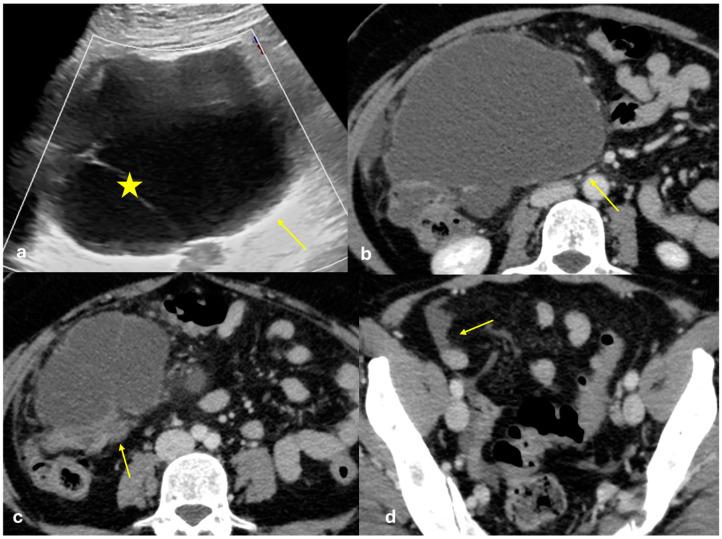

The peritoneum is a thin membrane that lines the abdominal cavity and covers the abdominal organs. It serves as a conduit for the spread of various pathological processes, including gas and fluid collections, inflammation, infections, and neoplastic conditions. Peritoneal carcinomatosis is the most common and well-known pathology involving the peritoneum, typically resulting from the dissemination of gastrointestinal and pelvic malignancies. However, numerous benign and malignant peritoneal diseases can mimic the imaging appearance of peritoneal carcinomatosis. The aim of this review is to revisit the anatomy of peritoneal compartments and elucidate the patterns of peritoneal disease spread. Emphasis is placed on identifying the distinctive imaging features of both neoplastic and non-neoplastic peritoneal diseases that differ from peritoneal carcinomatosis.

腹膜是一层薄的膜,它衬于腹腔内并覆盖腹部器官。它是各种病理过程扩散的通道,包括气体和液体聚集、炎症、感染及肿瘤性疾病。腹膜癌病是涉及腹膜的最常见且广为人知的病理情况,通常由胃肠道和盆腔恶性肿瘤的播散引起。然而,许多良性和恶性腹膜疾病可模仿腹膜癌病的影像学表现。本综述的目的是重新审视腹膜腔室的解剖结构并阐明腹膜疾病的扩散模式。重点在于识别与腹膜癌病不同的肿瘤性和非肿瘤性腹膜疾病的独特影像学特征。